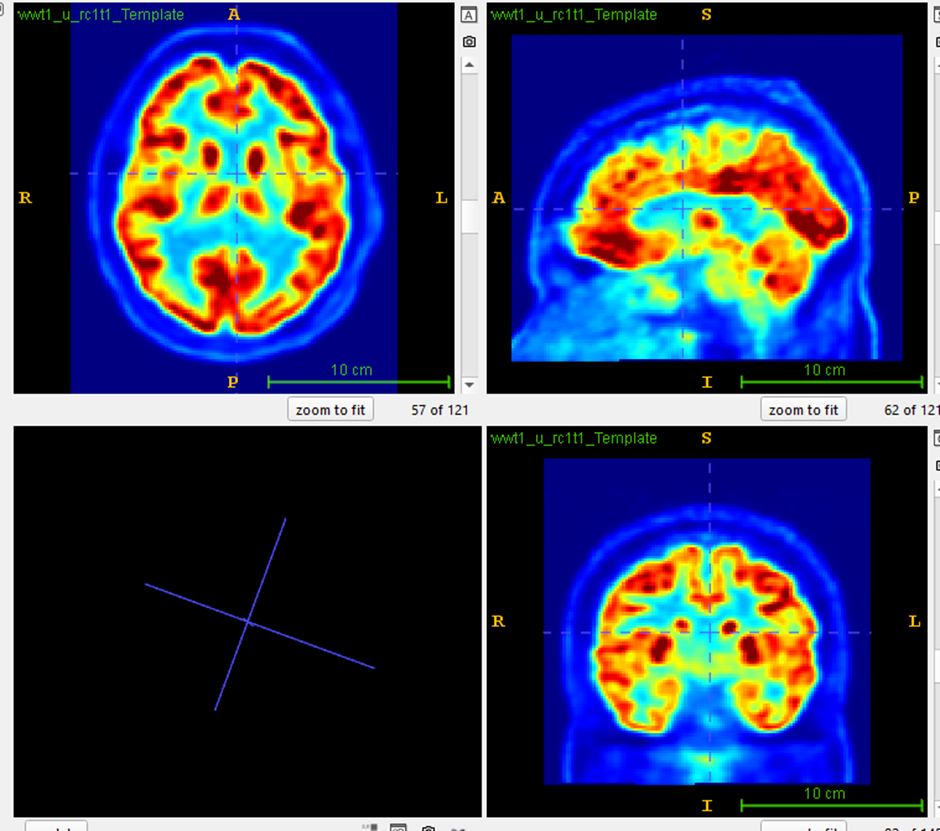

Anatomically Symmetrized FDG-PET Analysis

Nectara PASCOM generates a personalized symmetrical brain template using high-resolution T1-weighted and FLAIR MRI, ensuring voxel-wise alignment for accurate interhemispheric comparison.

Automated Asymmetry Index (AI) Calculation

Voxel-wise asymmetry is quantified using a robust AI formula and z-score thresholding. This enables objective detection of focal hypometabolism with optimized thresholds (Z4: z-score > 4).

Multimodal Integration

Seamlessly coregistered with MRI, Nectara PASCOM™'s output supports clinical decision-making in multidisciplinary team (MDT) discussions and surgical planning